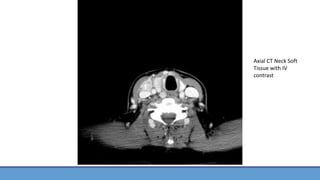

• CT Neck Soft Tissue w/ IV Contrast had been performed in ED prior to admission and ENT consult

Axial CT Neck Soft

Tissue with IV

contrast